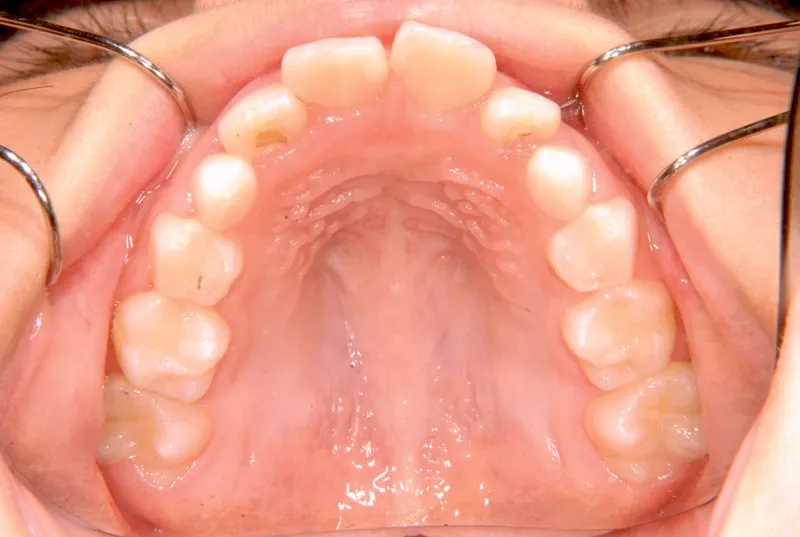

初診時年齢 小学校3年生 (女性) 主訴 出っ歯・前歯がゆがんでいる

診断名 叢生・上顎前突 装置名

状態 永久歯が生える隙間がない(叢生)

ガタガタ・でこぼこに生えている(叢生)

出っ歯(口元が出ている/上顎前突)

出っ歯と前歯のゆがみを主訴に来院されました。

低学年時は取り外しの装置を使用し、高学年になってからは見えにくい固定式の装置を使用して治療しました。

治療回数48回、7年2ヶ月の治療期間で矯正治療を終了しました。

主訴が改善され、ご満足頂きました。